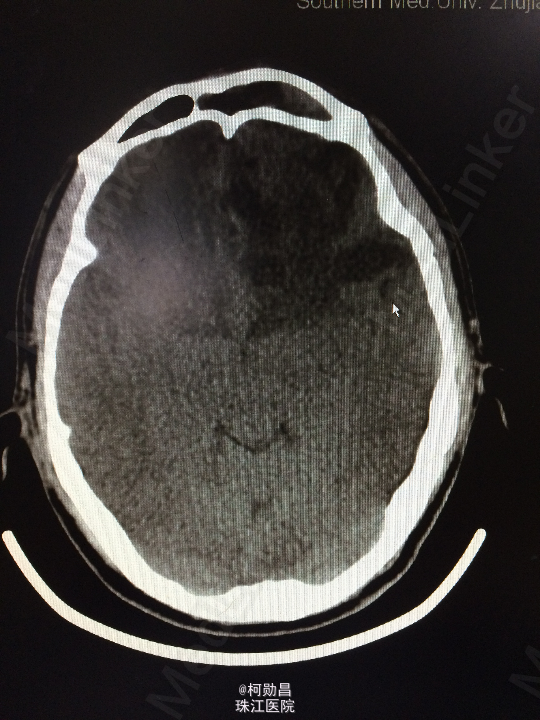

主诉:头痛伴左眼视力下降半年 病史:患者46岁男性,缘于半年前无明显诱因出现头痛,当时未予特殊处理,后症状进行性加重,并发左眼视力下降,于当地医院行头颅CT及MR检查提示颅内占位,为进一步治疗而入我院。 既往病史:5年前曾患鼻咽癌

查体:神志清楚,对答流利,左侧眼裂变小,左侧瞳孔散大,直径4mm,对光反射迟钝,左眼视力下降。右侧正常。 辅助检查:头颅MR提示前颅底筛沟通病变

诊断:鼻咽癌脑转移 处理:全麻下行颅筛沟通占位切除术,术后病理提示:鼻咽非角化鼻咽癌脑转移